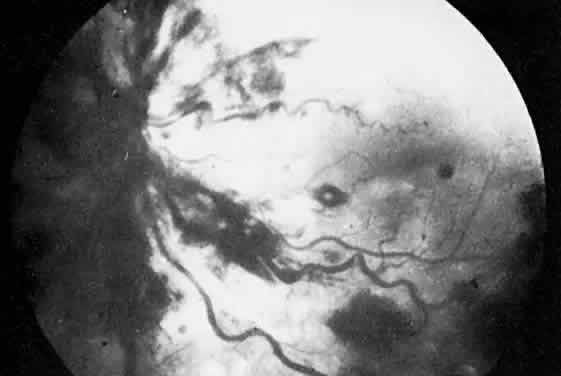

The classic ocular finding in DIC is serous retinal detachment64,65 (Fig. 5). The pathogenesis of these detachments involves choriocapillaris occlusion resulting in retinal pigment epithelial damage and subsequent loss of retinal pigment epithelial barrier and pump function. Fluorescein angiography confirms this pathophysiology, showing delayed filling of the posterior choroid with later pigment epithelial staining (Fig. 6). If the underlying DIC can be reversed, the retina may reattach, with return of vision. Other findings associated with DIC include retinal and vitreous hemorrhages.

Fig. 5. Serous retinal detachment in disseminated intravascular coagulation. (Hoines J, Buettner H: Ocular complications of disseminated intravascular coagulation [DIC] in abruptio placentae. Retina 9:107, 1989.)

Fig. 6. Delayed choroidal filling with pigment epithelial staining in disseminated intravascular coagulation. (Hoines J, Buettner H: Ocular complications of disseminated intravascular coagulation [DIC] in abruptio placentae. Retina 9:107, 1989.)